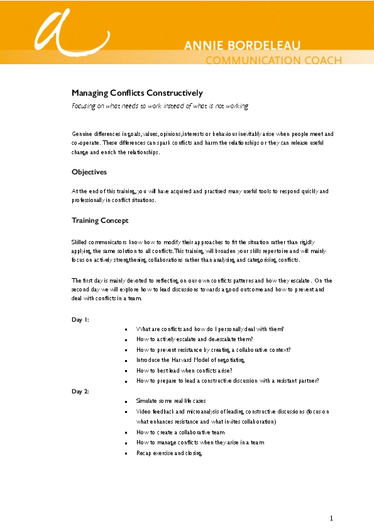

Press release: CRU326 members identified one genetic cause for male infertility

Press release: CRU326 members identified one genetic cause for male infertility

Fataler Fehler bei C11ORF70: Münstersche Uni-Mediziner identifizieren Genmutation als eine Ursache für männliche Infertilität

Fataler Fehler bei C11ORF70: Münstersche Uni-Mediziner identifizieren Genmutation als eine Ursache für männliche Infertilität